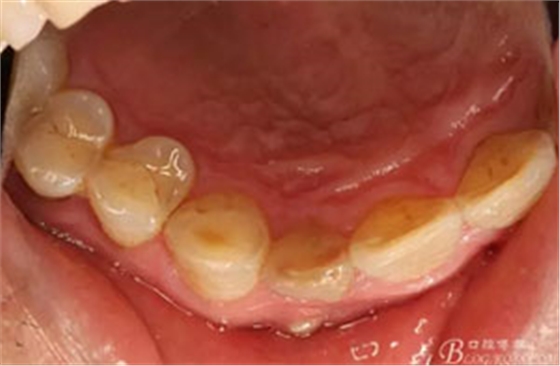

圖3.腭側(cè)觀;11腭側(cè)牙齦正常,21腭側(cè)樹脂充填完好